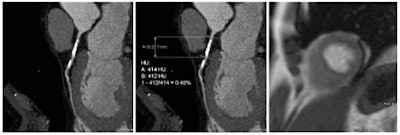

"One of the methods currently under investigation is CCO measurement," Vliegenthart told AuntMinnieEurope.com. "This measurement is based on a different principle than FFR-CT, as no computational fluid dynamics is used, but measurement of the gradient of CT density along the coronary artery. This is a semiautomated measurement with little reader interaction that can be performed on-site using dedicated software, in contrast to FFR-CT. We found excellent inter-reader agreement in a sub study (part of the manuscript). However, we did not compare these techniques directly, so we cannot state how well they compare in terms of outcomes."

This study compared its COO results with APMR, which has high sensitivity of 91% and specificity of 94% as compared with invasive FFR. The researchers examined 60 asymptomatic cardiac patients with extracardiac arterial disease (mean age 64.4 ± 7.7 years; 78% male) who underwent both CCTA and APMR. The study measured luminal CT attenuation values, or Hounsfield Units, in the coronary arteries from proximal to distal, with additional measurements across sites showing greater than 50% stenosis at CCTA.

The drop in CCO across vessels with hemodynamically significant stenoses was larger than that of vessels without associated ischemia, the group reported. The CCO decrease across stenoses with hemodynamic significance was 0.144 ± 0.112 versus 0.047 ± 0.104 across stenoses without hemodynamic significance (P = 0.003). Meanwhile, the CCO decrease in lesions with and without anatomical stenosis was similar (0.054 ± 0.116 versus 0.052 ± 0.101; P = 0.89).

Compared with previous reports on CCO, the method in this study was slightly altered, and based on semiautomated Hounsfield Unit measurements using curved multiplanar reconstructions. The method produced high reproducibility and excellent inter-reader agreement. An advantage of this approach is that CCO assessment requires less skill and may be performed faster and perhaps more easily in clinical practice.